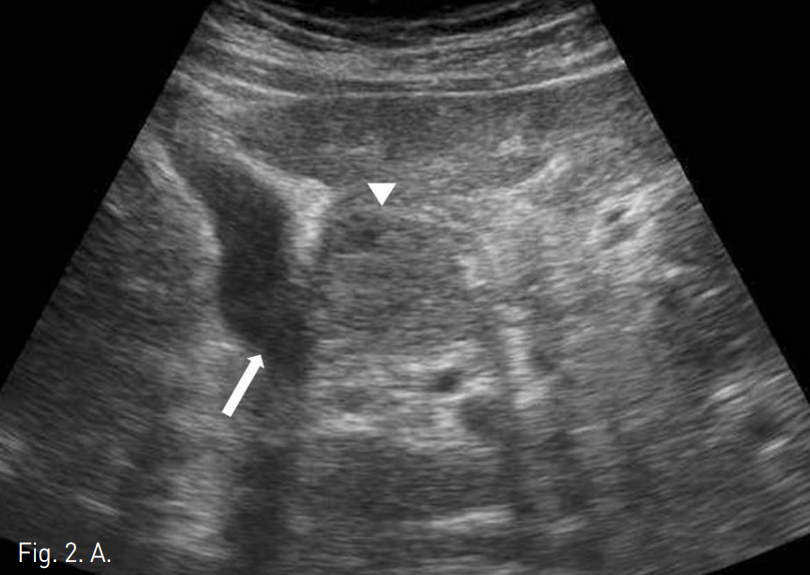

PEIT시행 후 ablation tip이 2.0cm인 RFA probe(Taewoong, Korea)로 국소소작을 시행하였다. 시술 한달 후와 4개월 후 시행한 추적검사 CT와 MRI에서 치료를 시행하였던 HCC 병변은 safety margin이 확보되었고 재발 소견은 보이지 않았다.

Fig. 3

Four months later, follow-up MRI demonstrated no evidence of tumor recurrence.